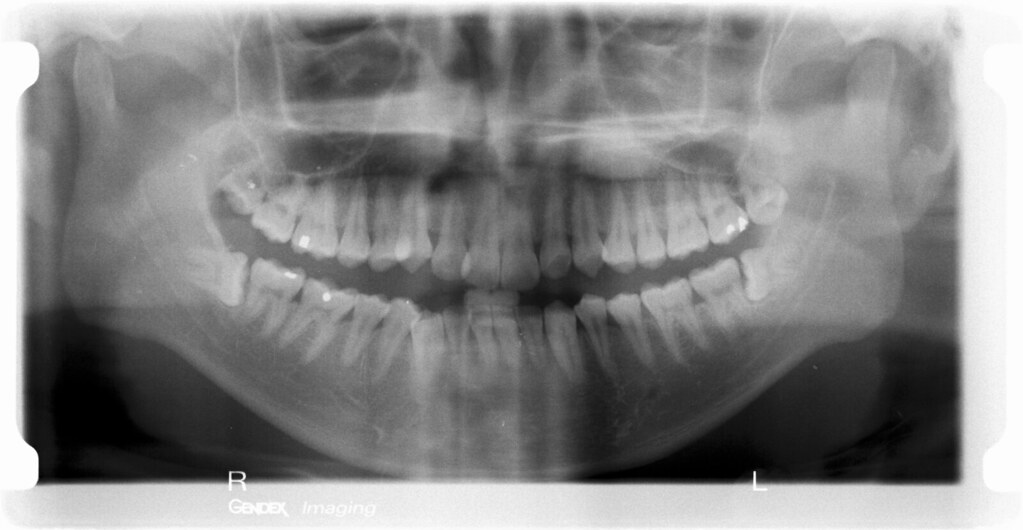

See how many teeth are still inside the gums, what position they are in, and how large they are. Here is a third kind of fish to breed. While somewhat gnarly, sure, but it’s still rather fascinating to see what it looks like as permanent teeth form within the skull before pushing out baby teeth.

Only your mouth is exposed to radiation, and at very low levels, so there is little risk to your baby. Here is a third kind of fish to breed. See how many teeth are still inside the gums, what position they are in, and how large they are. New born baby teeth xray. This is also called a panorex scan.

It is a useful way to see if you need any dental work before treatment starts. It can show cancer around these bones. See how many teeth are still inside the gums, what position they are in, and how large they are. This is also called a panorex scan or an opg. Of a patient isolated in white background

This is also called a panorex scan or an opg. While somewhat gnarly, sure, but it’s still rather fascinating to see what it looks like as permanent teeth form within the skull before pushing out baby teeth. New born baby teeth xray. See how many teeth are still inside the gums, what position they are in, and how large they.

This is also called a panorex scan or an opg. While somewhat gnarly, sure, but it’s still rather fascinating to see what it looks like as permanent teeth form within the skull before pushing out baby teeth. This takes pictures of the area around the upper jawbone (maxilla) and lower jaw bone (mandible). If playback doesn't begin shortly, try restarting.